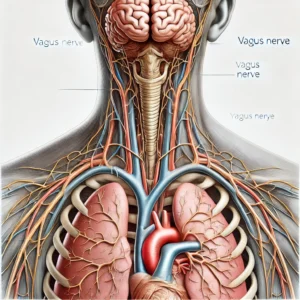

- The Fascinating Role of the Vagus Nerve in Health and Well-beingThe Fascinating Role of the Vagus Nerve in Health and Well-being The vagus nerve, a remarkable part of our nervous system, plays a crucial role in maintaining our overall health and well-being. Originating from the brainstem, this extensive nerve extends throughout the body, touching various organs and systems. The wanderer… Read more: The Fascinating Role of the Vagus Nerve in Health and Well-being